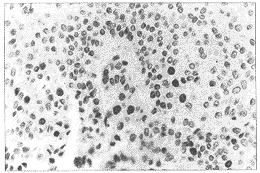

PCNA为颗粒型阳性,定位于细胞核,呈黄褐色(图1),每张切片选取10个不同视野用网 格测微尺记数100个网格内肿瘤细胞数及阳性核细胞数,计算阳性核细胞数占总的肿瘤细胞 数的百分比,再取10个视野的平均值作为该患者膀胱移行细胞癌的PCNA值。VWF:Ag以血管内 皮细胞染成棕黄色为阳性(图2),单个的内皮细胞着色也判断为阳性。用OLYMPUS显微镜在 200倍视野下对每例膀胱移行细胞癌的VWF:Ag染色切片选取10个血管数目最多的视野计数其 血管数,计算其平均数。

图1 PCNA在膀胱移行细胞癌组织中的表达:

PCNA为颗粒型阳性,部位在细胞核,呈黄褐色LSAB法×400